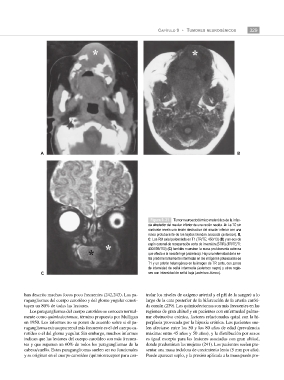

Figura 9–31 Tumor neuroectodérmico melanótico de la infan-

cia alrededor del maxilar inferior de una recién nacida. A: La TC sin

contraste revela una lesión destructiva del maxilar inferior con una

masa protuberante de los tejidos blandos asociada (asterisco). B,

C: Las RM axial potenciada en T1 (TR/TE; 450/13) (B) y en eco de

espín coronal de recuperación corta de inversión (STIR) (TR/TE/TI;

4300/56/150) (C) también muestran la masa protuberante extensa

que afecta a la nasofaringe (asterisco). Hay una intensidad de la se-

ñal predominantemente intermedia en las imágenes potenciadas en

T1 y un patrón heterogéneo en la imagen de TR corto, con zonas

de intensidad de señal intermedia (asterisco negro) y otras regio-

C nes con intensidad de señal baja (asterisco blanco).